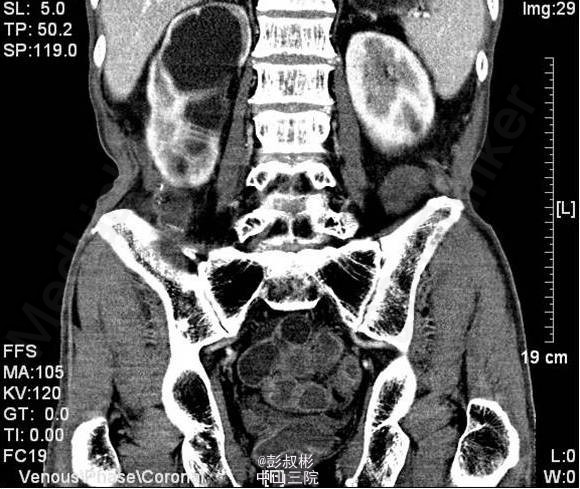

3、既往病史:既往“高血压”病史20年余,自服硝苯地平。“脑梗死”病史半年余,规律服用抗凝药物。 4、入院查体:无明显阳性体征。 实验室检查: 2015-01-11 肌酐101.2umol/L 。 2015-01-13总前列腺特异性抗原1.1ng/ml,游离前列腺特异性抗原0.3ng/ml。 2015-01-15 白细胞总数3.21x10E9/L,红细胞总数2.61x10E12/L,血红蛋白浓度78g/L,肌酐131umol/L ,白蛋白27g/L。 影像学检查: 2014-12-30心电图:完全性右束支传导阻滞。 2014-12-30全腹螺旋CT 检查所见:1、前列腺增生并钙化,建议MRI增强进一步检查除外合并肿瘤性病变。2、右侧盂管交界处结石并重度梗阻性肾积水,右肾结石;左肾多发钙化灶;左肾多发囊肿。3、慢性胆囊炎。4、双肺下叶多发小结节。 2015-01-14核素肾动态显像+GFR双血浆测定:右肾灌注、功能重度受损。左肾灌注正常,功能中度降低。肾小球滤过率:左肾为23.4ml/min,右肾为9.0ml/min。 2015-01-15彩超心脏:二尖瓣反流(轻度)。三尖瓣反流(轻度)。左室收缩功能正常。左室舒张功能减退。

5、目前诊断:1、右侧重度肾积水2、双侧肾结石3、左肾多发囊肿4、慢性胆囊炎